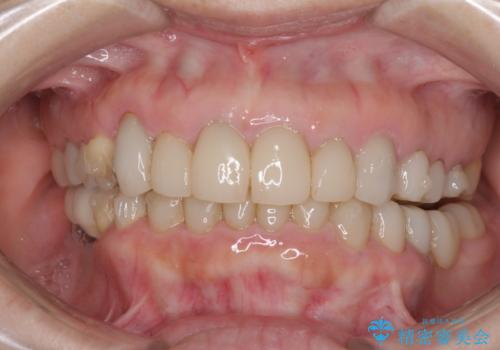

- 下顎の前歯に激痛を覚えて来院された患者様です。

取り急ぎ下顎前歯数歯の根管治療を、銀座しらゆり歯科医院長の林先生にお願いし、それ以外に気になっている、不自然な色調のクラウン、金属部分が見えてブラッシングがしにくいインプラント補綴、口元の突出感、出血のしやすい歯周ポケットなど、全てを解決するための治療を行うこととしました。

期間と費用はかかりましたが、気になっていた部分全てを改善でき、患者様には大変満足していただきました。